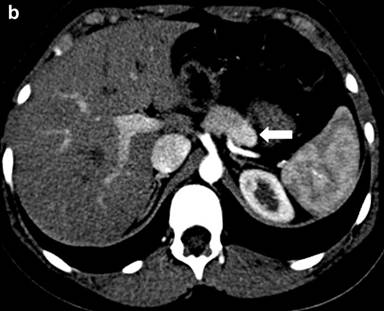

An abdominal contrast-enhanced computed tomography scan showed a 10x12x17 mm, small, well-demarcated, heterogeneously enhancing lesion within the body of pancreas without dilatation of pancreatic duct. No evidence of lymphadenopathy or distant metastasis was identified (Figure 1). Subsequently, patient was scheduled for laparotomy.

Figure 1. Coronal (a.) and transverse (b.) views of abdominal contrast-enhanced computed tomography scans: showing a 10x12x17 mm, small, well-demarcated, heterogeneously enhancing lesion within the body of pancreas (white arrow) without dilatation of pancreatic duct. No evidence of lymphadenopathy or distant metastasis was identified. |